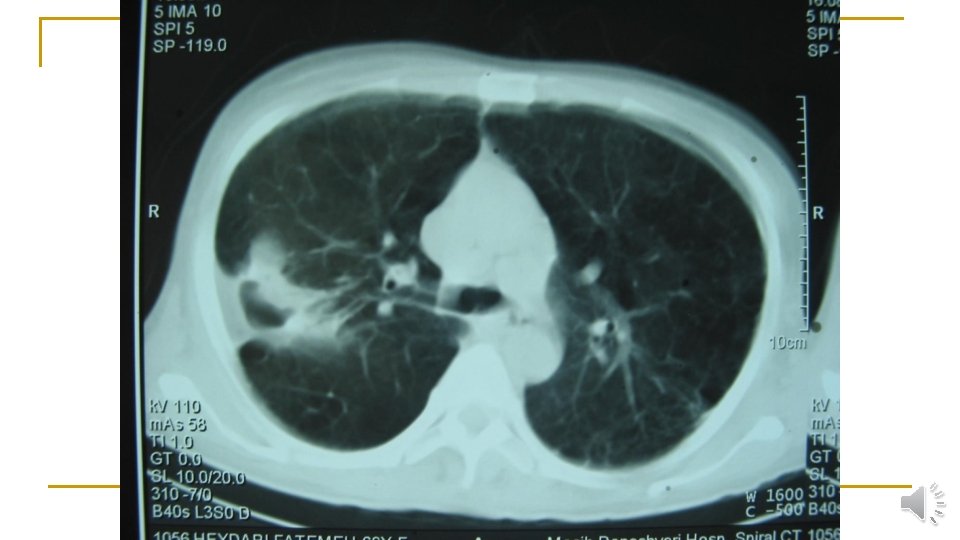

Lung CT scan